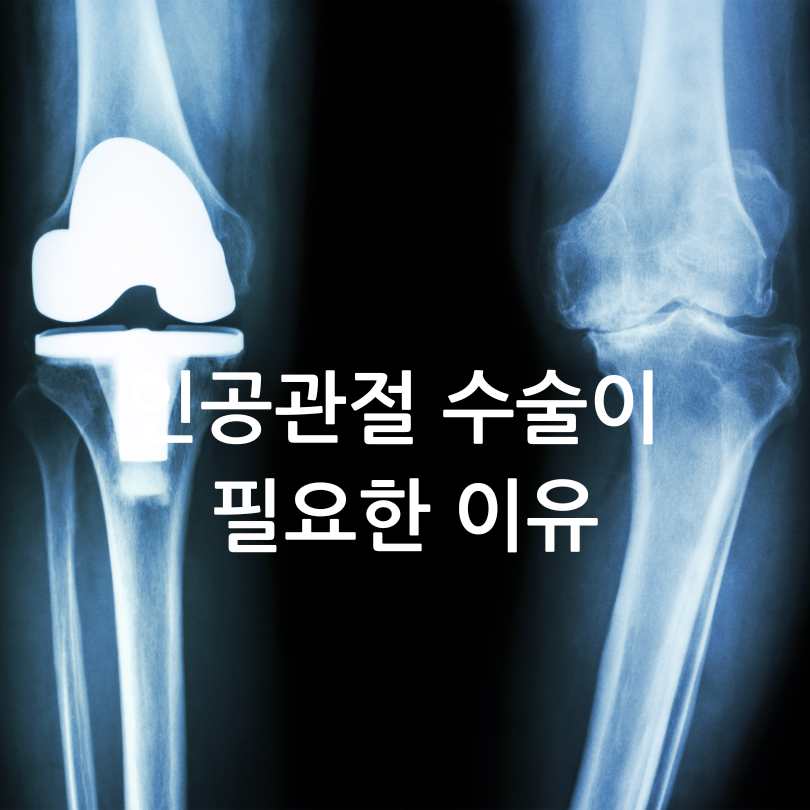

인공관절 수술이 필요한 이유

노년층에게 가장 흔한 질환 중 하나가 바로 '퇴행성 관절염'입니다.

관절의 연골이 닳아서 생기는 이 질환은, 시간이 지날수록 극심한 통증을 유발하며

보행 장애, 낙상 위험까지 높여 삶의 질을 떨어뜨립니다.이런 경우, 무릎 인공관절 치환술이라는 수술이 치료 방법으로 권해지곤 합니다.

하지만 문제는, 이 수술이 한쪽 무릎 기준 약 200~300만원 이상 들어간다는 점이죠.

특히 저소득층 노인분들에겐 큰 부담입니다.